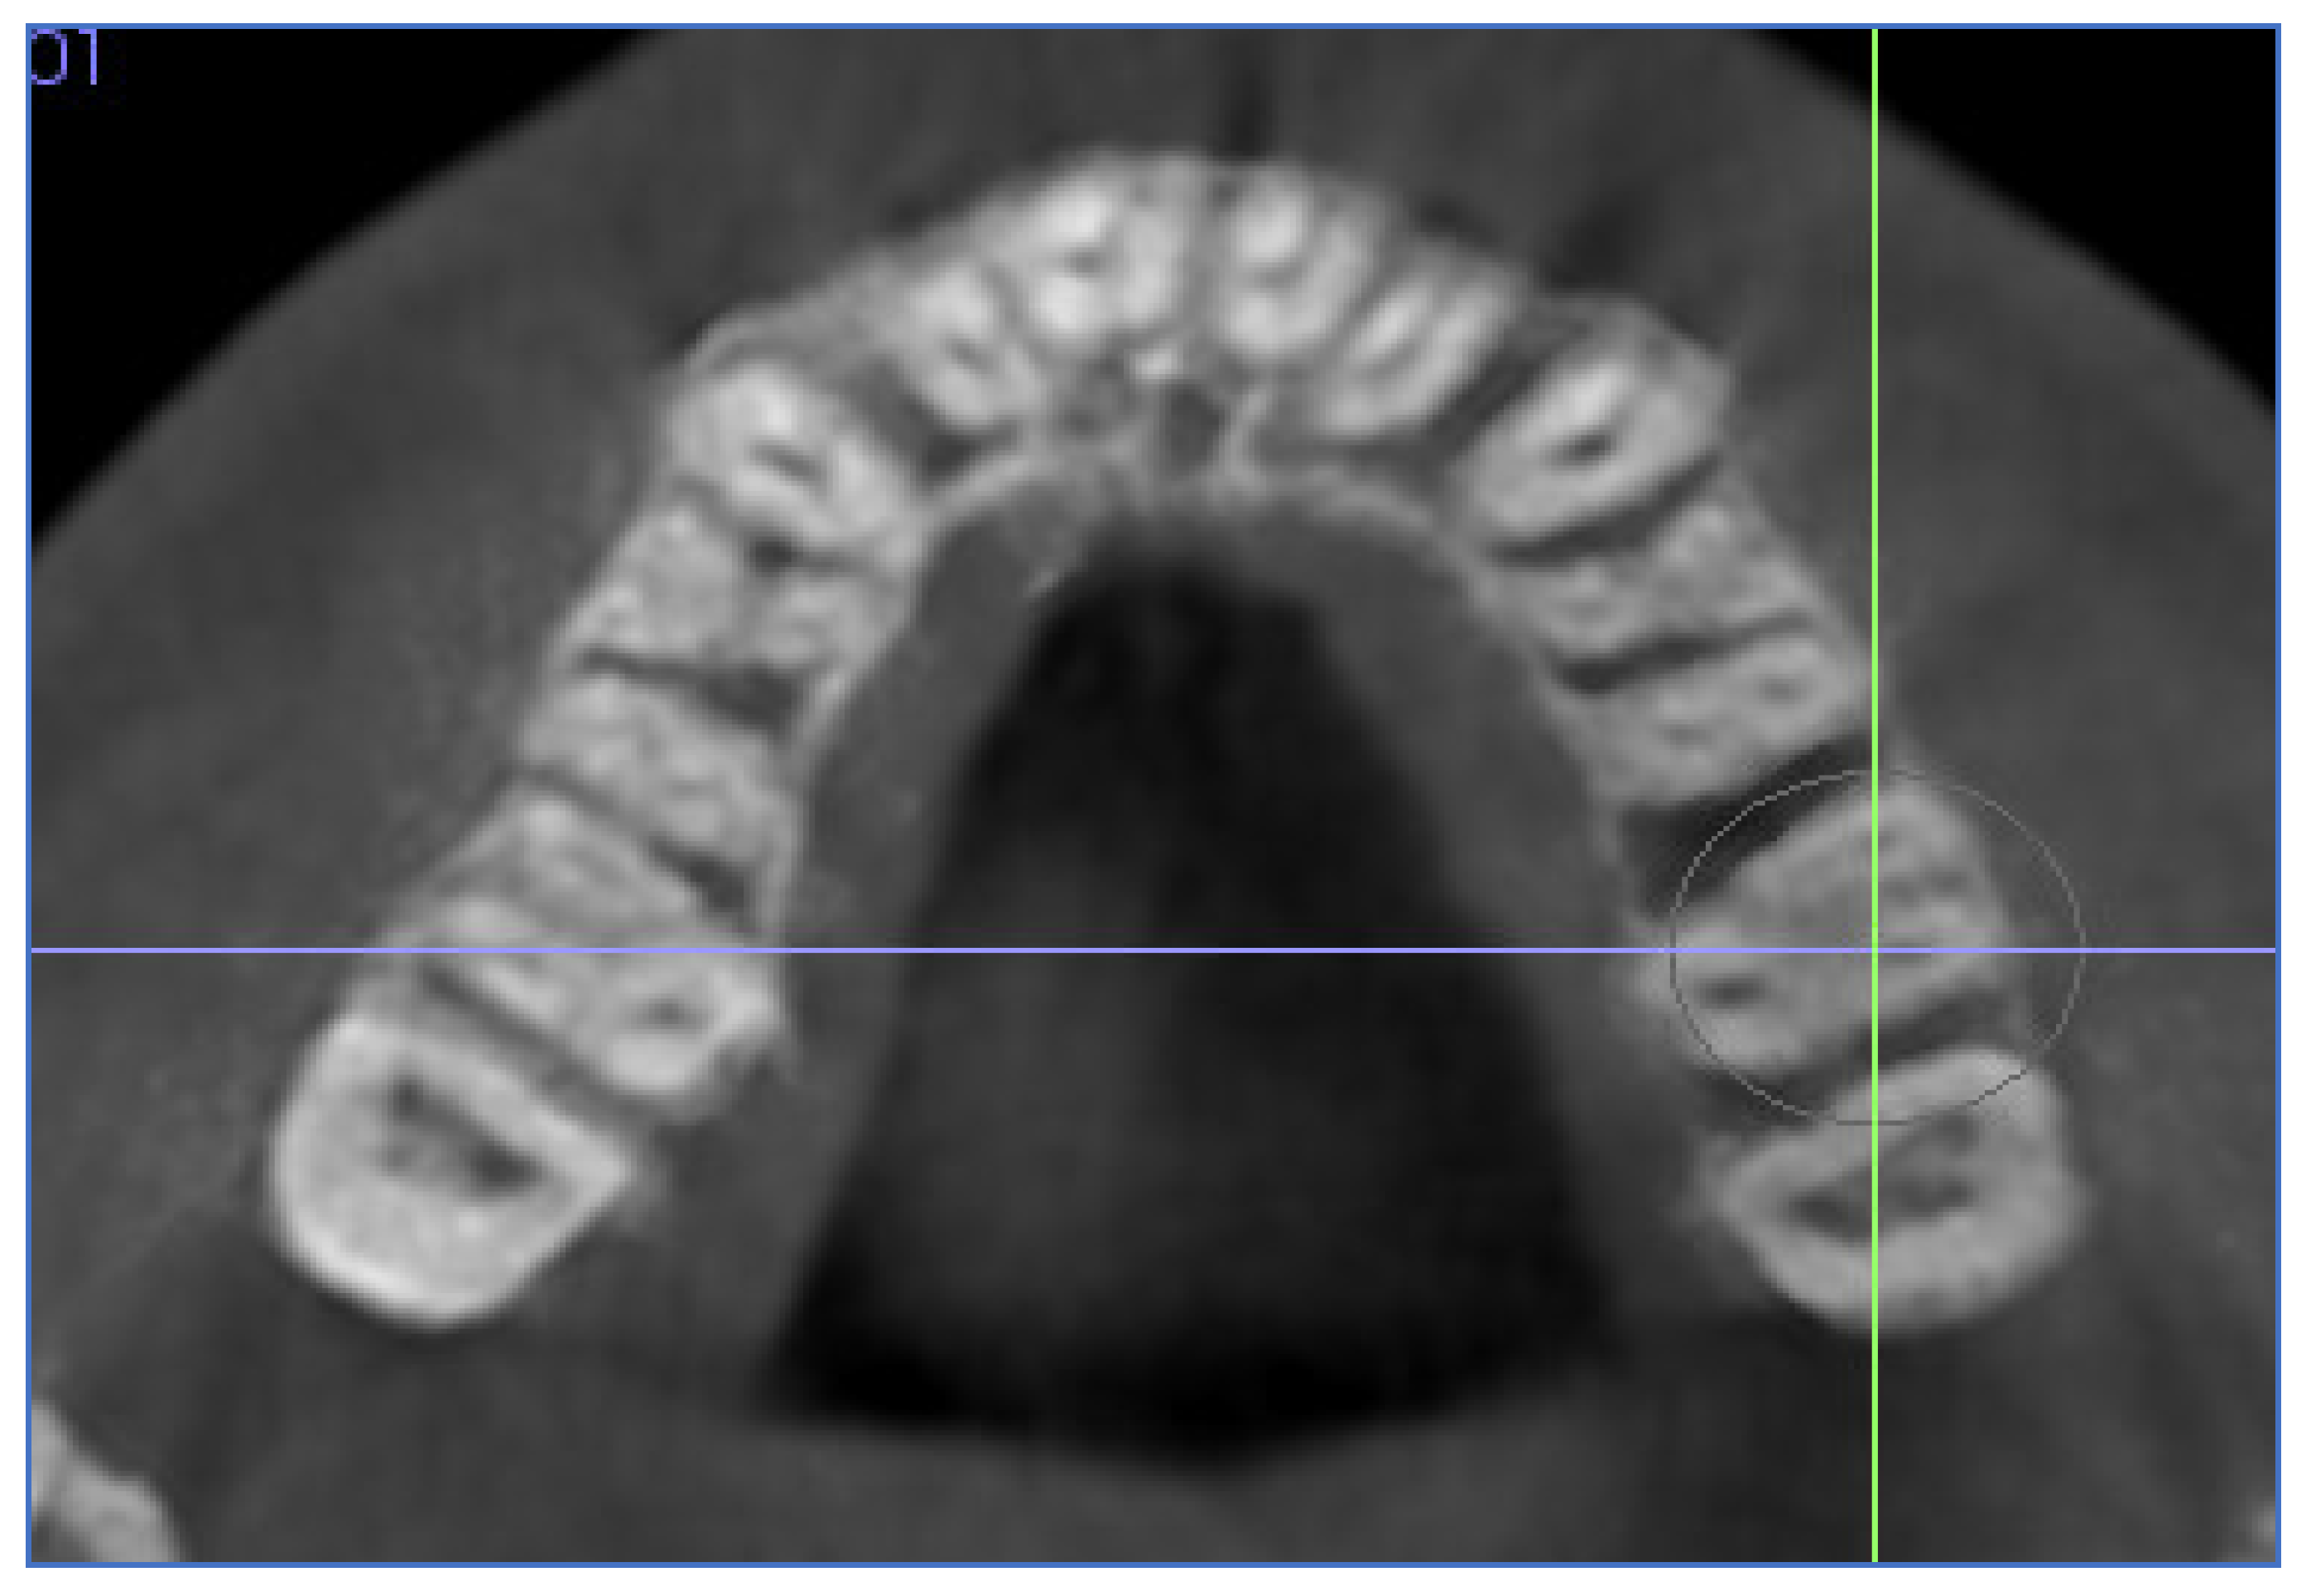

| Palatal suture opening (SO) | Distance between the external right and left maxilla edges in the axial view generating a slice in the horizontal plane, allowing a good visualization of the midpalatal suture at first and second premolar, and first molar. The edges were identified with a small point on an axial cross-sectional slice at the level of the first molar trifurcation. | ![]() |